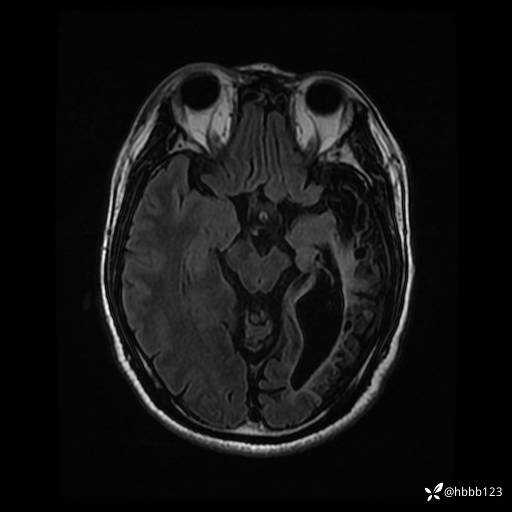

患者男,43岁。

简要病史:癫痫患者复诊,昨日发作5-6次,建议住院进一步治疗。

入院完善脑癫痫组合序列:

T2 Flair: